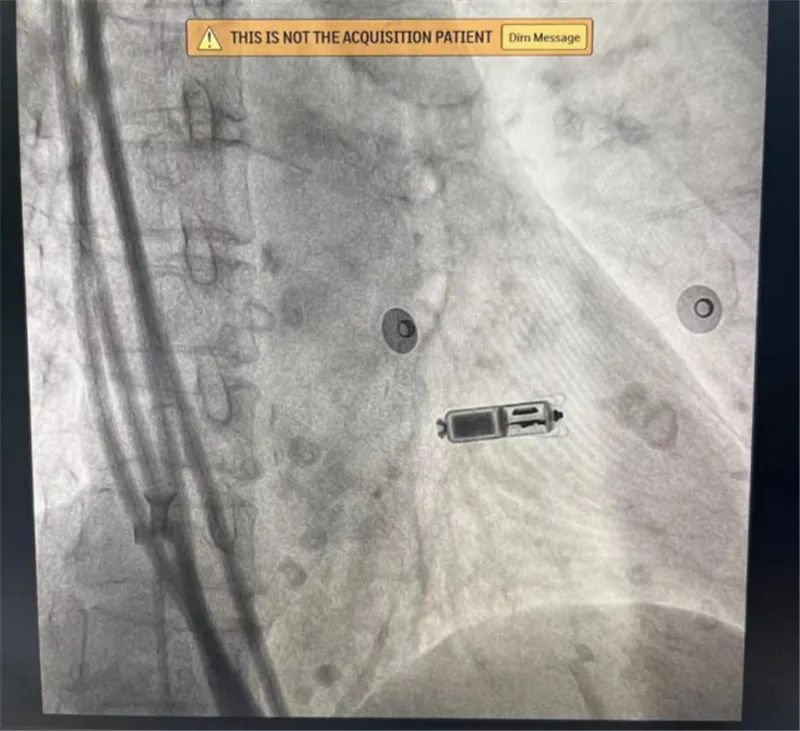

术后心脏起搏器影像图